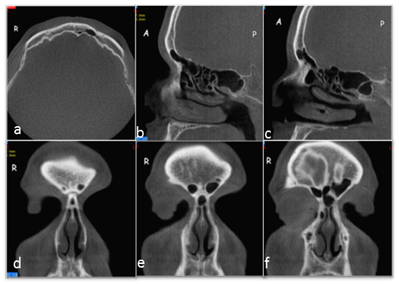

In the DVT scans, both agenesis (on the right) and aplasia (on the left) were seen in one case (0.24%; Fig. 2). The results from the present study are summarized in Table 1. The weighted kappa values for intra-observer reliability were 0.89 and 0.93 for the first and second observer, respectively. The weighted kappa value for inter-observer reliability between observers 1 and 2 was 0.86.

Fig 2

Unilateral absence of the frontal sinus; on the right, the absence of the frontal sinus, and on the left, the limited aeration of the frontal sinus; axial view (A), right sagittal view (B), and left sagittal view (C); sequential coronal slices of frontal sinuses (D, E, F).

The variations in the anatomy of the frontal sinus may be critical for morphological or forensic investigations and for neurosurgeons performing pterional or supraorbital craniotomy because of the proximity of the sinus to the orbit and the anterior skull base [5]. The frequency of bilateral absence of the frontal sinus has been reported in 3-4% to 10% of several populations [1]. However, this frequency was significantly higher in some populations, including Alaskan Eskimos (25% in males and 36% in female) and Canadian Eskimos (43% in males and 40% in female) [21,22]. According to the literature, the frequency of a bilateral absence of the frontal sinuses (Fig. 3) in this study was lower than that reported for most ethnic populations. In addition, previous researchers have reported that a greater frequency of bilateral frontal sinus agenesis occurs among females than among males, which is similar to the findings in our study (Table 1) [1,5, 21].

Fig 3

Bilateral absence of the frontal sinuses; axial view (A), right sagittal view (B), left sagittal view (C); sequential coronal slices of frontal sinuses (D, E, F).